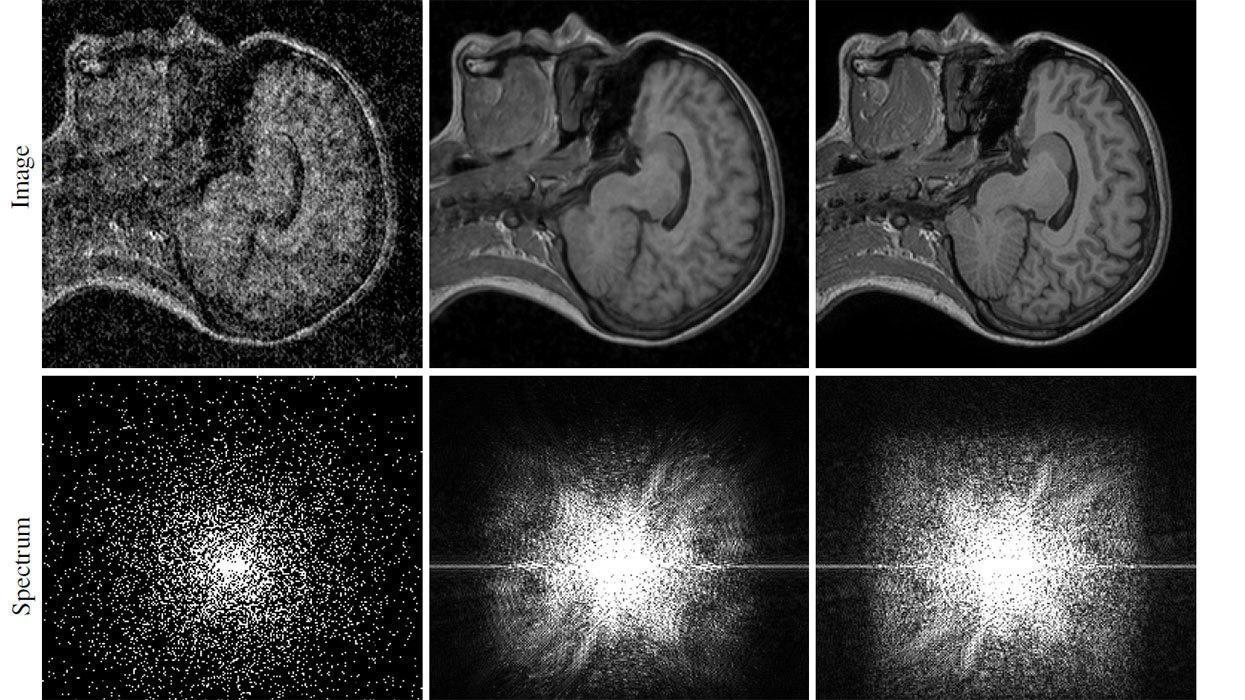

Качество и время срабатывания в зависимости от числа фильтров . Согласно авторам исследования, архитектура сети влияла на качество больше, чем размер обучающей выборки .